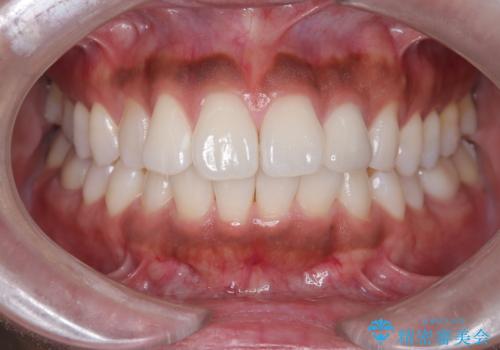

- 「前歯の歯の色が気になる」を主訴に来院された患者さんです。歯の大部分がプラスチックの材料で治療されていました。そこが劣化し変色していたためオールセラミッククラウンで治療を行いました。前歯の色を全体的に白くするために当院でオフィスホワイトニングも行いました。

左上2番の大部分がプラスチックの材料で治療されていました。そのプラスチックの材料が劣化して変色し虫歯になっている状態でした。なので古いプラスチックの材料を全て除去し、その下の虫歯を取った後、オールセラミッククラウンで治療を行いました。オールセラミッククラウンを装着する前に当院にてホワイトニングを行いました。